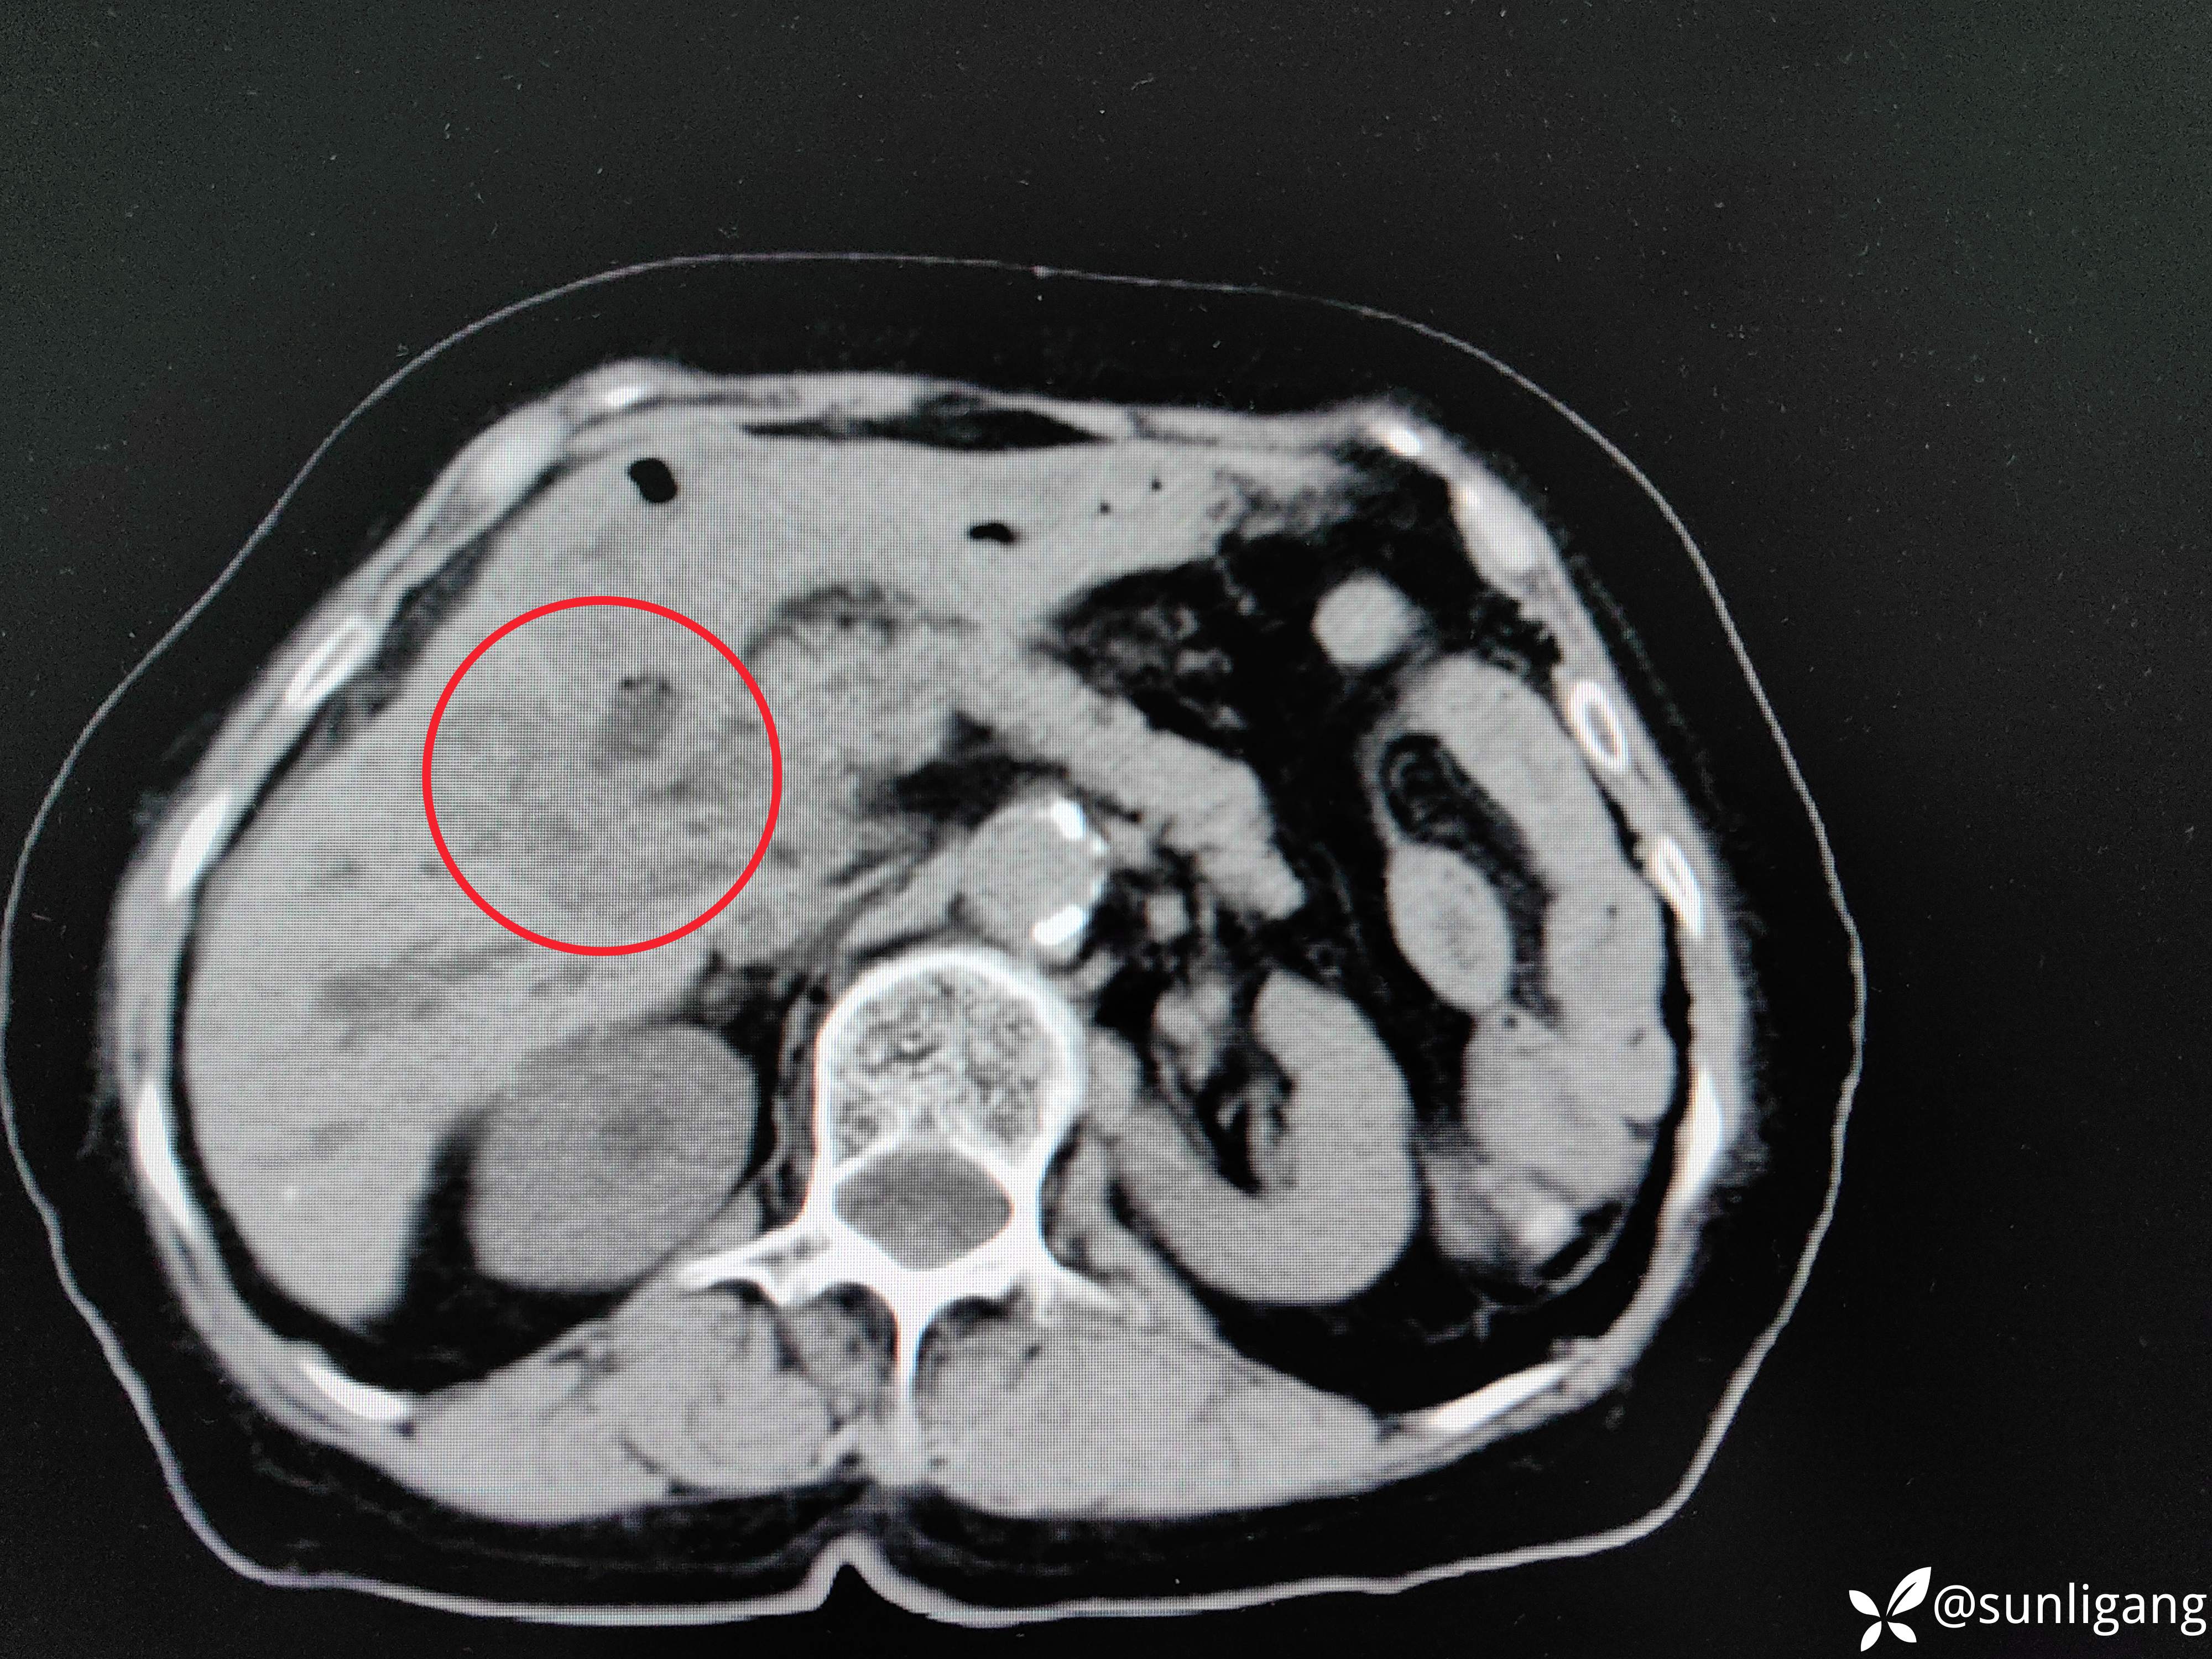

胆囊周围靠近肝脏一侧有明显的不均质低密度影

动脉期

增厚的胆囊壁及胆囊周围轻度强化的不均质组织、胆囊壁强化明显,还可见到右肝钙化点